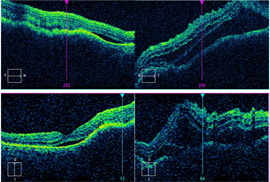

Optical coherence tomography through the macula of the right eye demonstrated a clear vitreous, normal retinal laminations, and mild irregularity of the retinal pigment epithelium band within the fovea. There was no intraretinal or subretinal fluid. There was thickening and consolidation of the submacular choroid with hyporeflective lamellae within the lesion and no normal choroidal vasculature visible in this area. B-scan ultrasonography demonstrated a plaque-like, hyperechoic choroidal lesion with shadowing posterior to the lesion.

Figure 2. Spectral-domain optical coherence tomography (SD-OCT) demonstrating intraretinal fluid, and subretinal fluid with subretinal fibrinoid response bilaterally. |